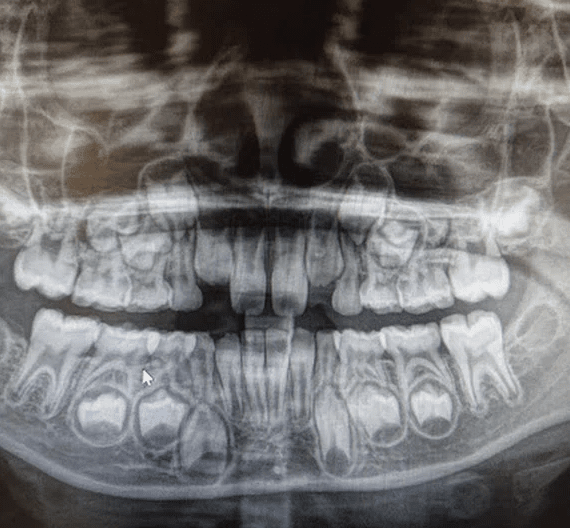

브라질의 한 소녀가 단순 유치 발치를 위해 병원을 찾았다가 전 세계적으로 유례없는 희귀 사례의 주인공이 됐다. 구강 내 치아 개수가 80개를 넘긴 사례는 극히 드물며, 이번 발견은 단순한 치과 이슈를 넘어 유전학과 발달의학까지 파장을 불러일으키고 있다. 11세 소녀의 엑스레이에는 유치 18개, 영구치 32개, 여기에 과잉치 31개까지 확인되면서 총 81개의 치아가 존재하는 것으로 나타났다. 일반적인 성인 치아 수가 32개라는 점을 감안하면 2.5배에 달하는 수치다.

이번 사례는 ‘다발성 과잉치증(multiple hyperdontia)’이라는 치과적 이상 현상으로 분류된다. 일반적으로 과잉치는 1~2개 정도가 드물지 않게 발견되지만, 10개를 넘는 경우는 희귀 질환 수준으로 여겨진다. 30개 이상의 과잉치가 동반된 경우는 전 세계적으로도 학계 보고가 손에 꼽힐 만큼 드물다. 문제는 과잉치가 단순히 숫자의 문제가 아니라 기능적, 구조적, 심미적 영향을 모두 유발할 수 있다는 점이다. 정상적인 치열 배열을 방해할 뿐만 아니라, 주변 치아의 뿌리를 압박하거나 턱뼈의 성장에 간섭할 위험도 존재한다.

이처럼 비정상적인 수의 치아를 가진 경우 단순 발치나 교정만으로는 해결이 어렵다. 특히 잇몸 깊은 층에 묻혀 있는 과잉치는 치아 형태가 정상이거나 뼈 속에 포함돼 있어 외형만으로는 구분이 힘들다. 무분별한 제거는 턱뼈 손상이나 신경 자극을 유발할 수 있기 때문에, 정밀한 영상진단과 협진 시스템이 핵심이다.